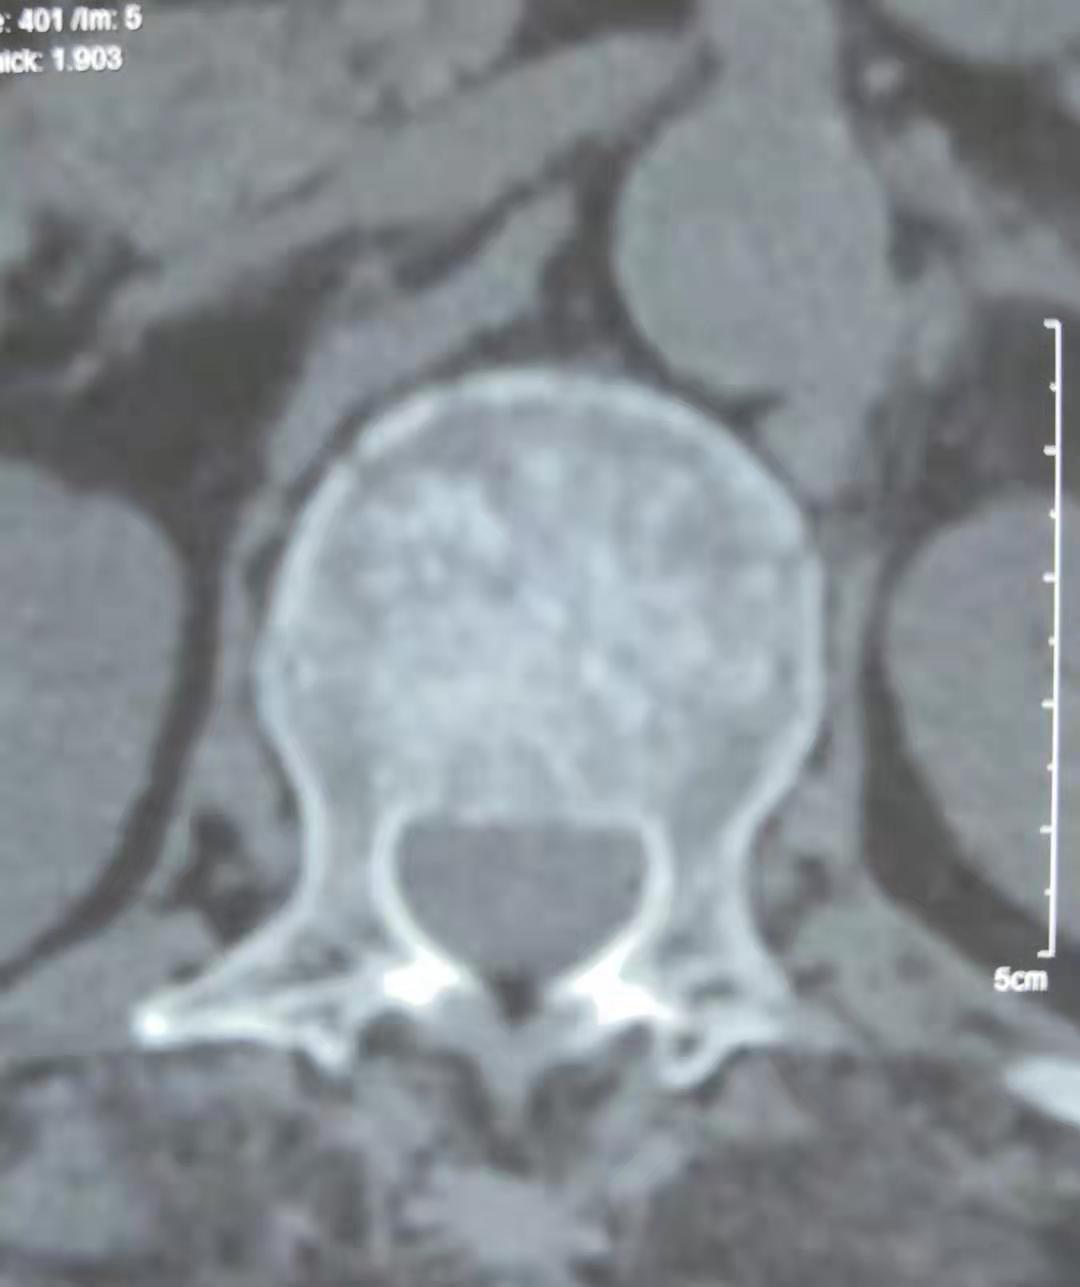

单纯腰椎骨折的背后,还发现了一个被压碎的血管瘤。而且其余椎体还有几个小的血管瘤。这就不是单纯骨折,而是病理性骨折。符合患者在轻微运动下就发生骨折的事实。